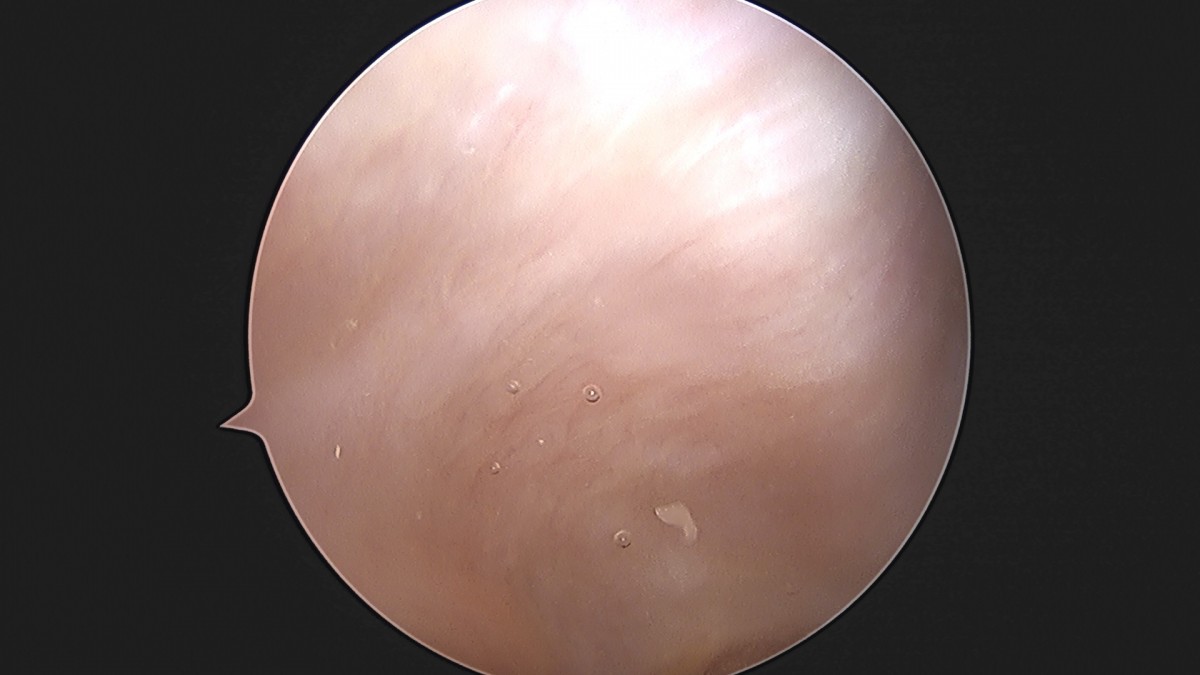

이재상원장님 무릎 반월상 연골판 절제술 최용O 환자

dae765e4d9ac96aee867c9d6292d8784_1758005820_5926.jpg